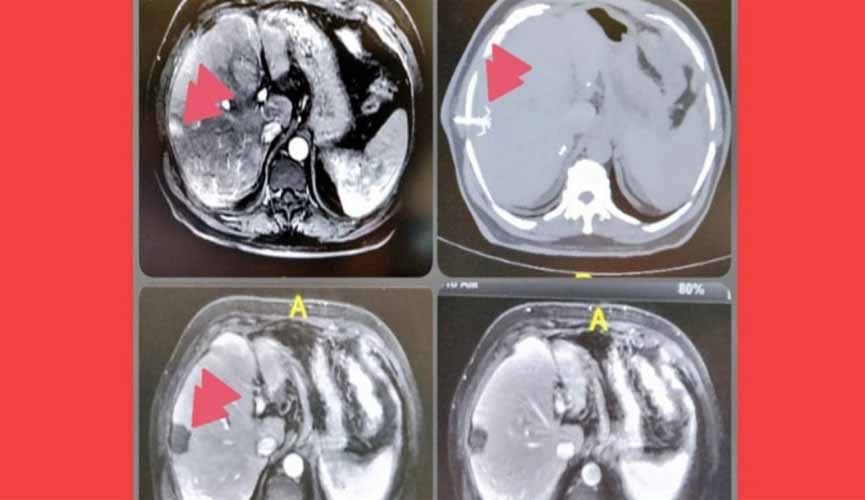

Pesquisadores da USP descobrem tratamento que destrói câncer em 4 minutos

Chamada de ablação, a técnica utiliza radiação micro-ondas para “torrar” as células cancerígenas